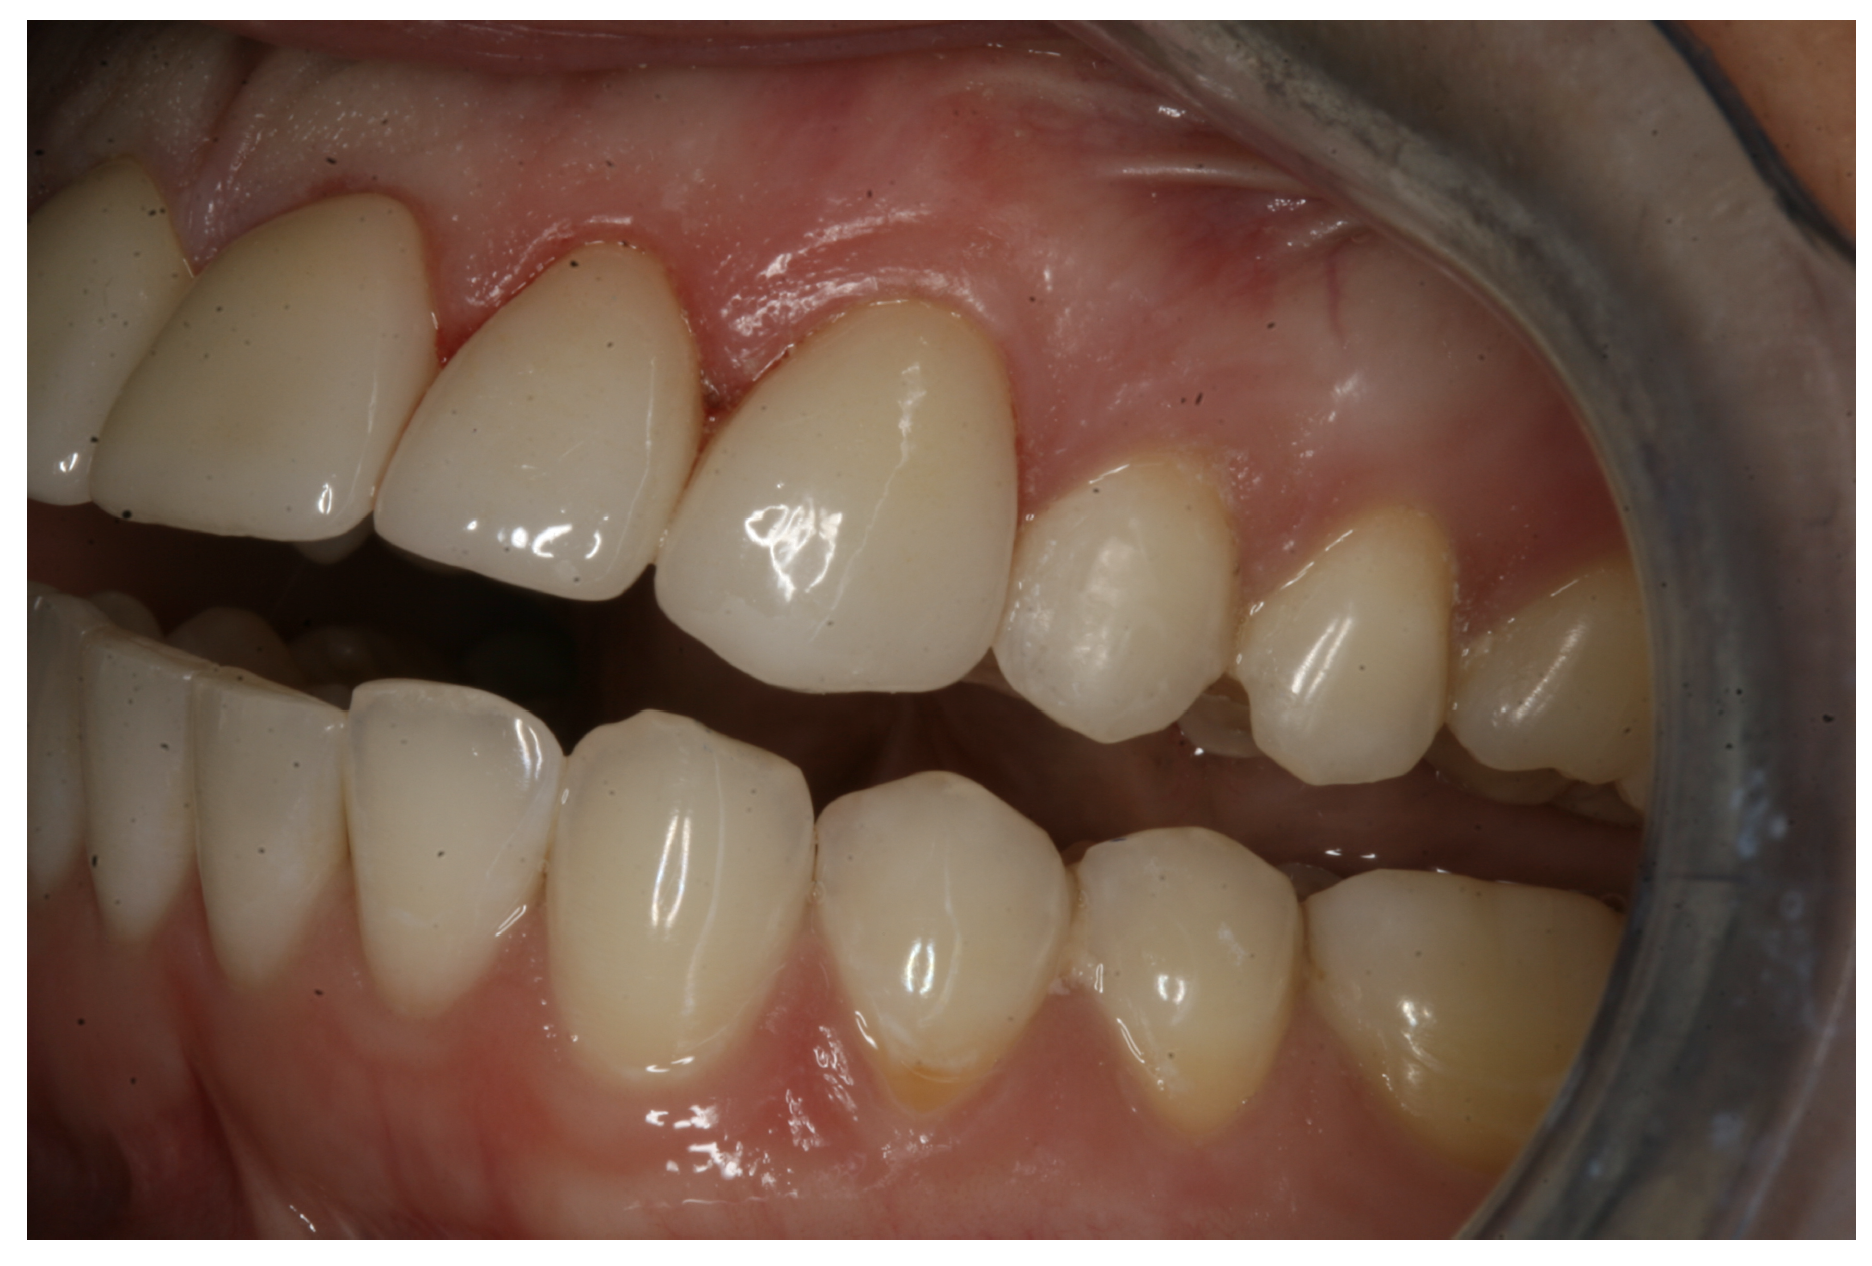

In another case, the patient presented with very thick, bulky, over-contoured veneers done on teeth Nos. 7 through 10 when she was a teenager. There also was some recession and staining at the margins (Figure 12). The clinician decided to restore teeth Nos. 6 through 11. A preparation design was required with provisionals removed. As tooth structure could not be regrown, the practitioner made the best of the situation. There was good gum health, which is important for isolation and marginal seal. The clinician cemented with a universal, doing six units at one time. Minimal cleanup was required. At a 1-month follow-up visit, although tissue still was settling in, the contours were natural. After a year (Figure 13), the gum filled in nicely and was in excellent health, and there was good color stability and seamless marginal integrity.